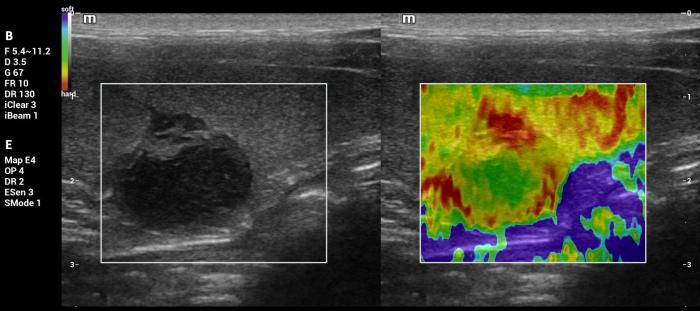

Además de la medición cuantitativa de la velocidad de la onda de corte expresada en metros por segundo (m/s), el sistema Natural Touch Elastography® (Mindray MX7) dispone de una función complementaria de representación cualitativa y semicuantitativa de la rigidez tisular (Figura1-4). Esta herramienta permite asignar valores numéricos y porcentajes relativos al grado de dureza o blandura del tejido evaluado y facilita la comparación visual y numérica entre diferentes regiones de interés dentro de un mismo órgano, incluyendo la relación entre una lesión focal y el parénquima esplénico adyacente.

De acuerdo con la documentación técnica del fabricante, esta funcionalidad se basa en el análisis de la respuesta tisular al impulso acústico y en algoritmos de seguimiento por radiofrecuencia, lo que contribuye a una evaluación intraorgánica más precisa. Si bien estos valores no sustituyen las mediciones cuantitativas en m/s ni cuentan con puntos de corte validados para la diferenciación diagnóstica, su utilización aporta información complementaria útil para la interpretación clínica de los hallazgos elastográficos, especialmente cuando se integra con la evaluación en modo B y Doppler.

Hallazgos elastográficos (Natural Touch Elastography®): la lesión mostró una rigidez similar al parénquima esplénico circundante, con valores que no superaban los rangos normales descritos para bazo canino3,4 (Figura 9-10). La uniformidad de las mediciones, sin artefactos relevantes y con estabilidad entre adquisiciones consecutivas, aumentó la confiabilidad de la evaluación.

Interpretación: la correlación entre un patrón en modo B hipoecoico bien delimitado, vascularización moderada y una rigidez similar al resto del parénquima esplénico es coherente con lesiones benignas, entre ellas la hiperplasia nodular y algunos hematomas en fase temprana. El resultado histopatológico confirma una condición benigna, lo que coincide con el comportamiento elastográfico observado.